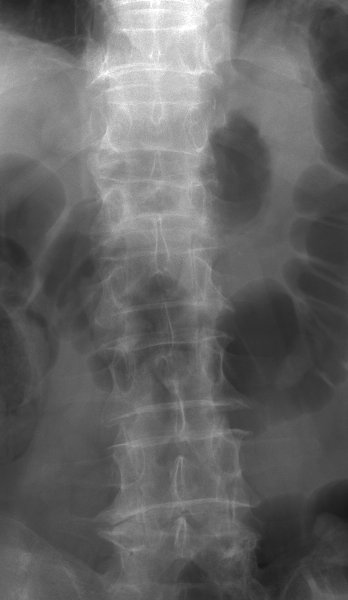

Return to Compression Fracture (Lumbar)